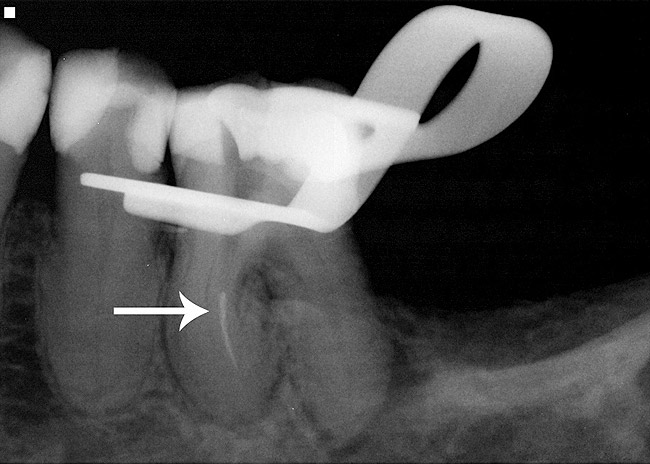

Even with the best preventive measures, endodontic rotary files can still separate within a canal (Figure 4). Although there are many file removal systems on the market today, the chance of successfully removing a broken file depends mainly on where it is located within a canal and the canal morphology. A study by Shen showed that the removal of a fractured NiTi instrument is more influenced by tooth anatomy, degree of root canal curvature, and fragment location than a specific technique.10 A study by Souter concluded that the limited success of file removal, increased risk of perforation, and reduced root strength suggest that file removal beyond the curved portion of the root should not be routinely attempted.11

Fig 4. Radiographic example of a separated endodontic rotary NiTi file.

Figure 4